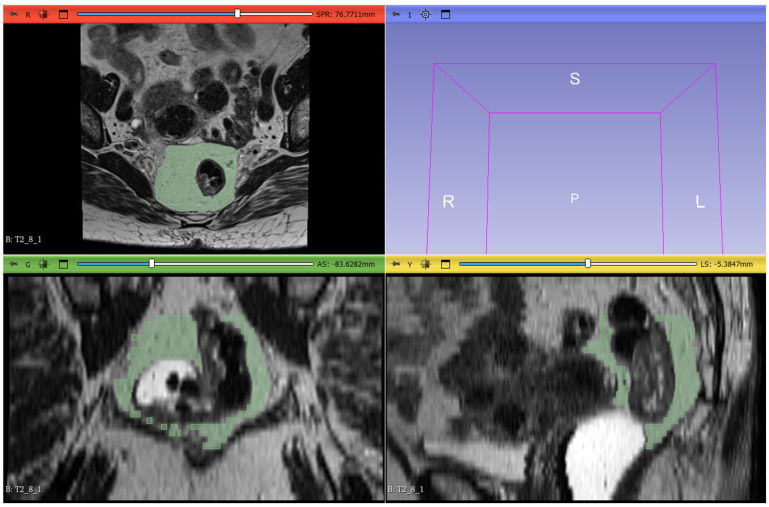

Methods: We conducted a retrospective analysis of adult patients with LARC who underwent pre- and post-nCRT MRI scans. Patients were classified as good responders (Group 0) or poor responders (Group 1) based on MRI findings, including tumor volume reduction, signal intensity changes on T2-weighted and diffusion-weighted imaging (DWI), and alterations in the circumferential resection margin (CRM) and extramural vascular invasion (EMVI) status. Classification criteria were based on the established literature to ensure consistency. Key clinical and imaging parameters, such as age, TNM stage, CRM involvement, and EMVI presence, were recorded. A radiomic model was developed using the LASSO algorithm for feature selection and regularization from 107 extracted radiomic features.

Results: We included 44 patients (26 males and 18 females) who, following nCRT, were categorized into Group 0 (28 patients) and Group 1 (16 patients). The pre-treatment MRI analysis identified significant features (out of 107) for each sequence based on the Mann-Whitney test and t-test. The LASSO algorithm selected three features (shape_Sphericity, shape_Maximum2DDiameterSlice, and glcm_Imc2) for the construction of the radiomic logistic regression model, and ROC curves were subsequently generated for each model (AUC: 0.76).